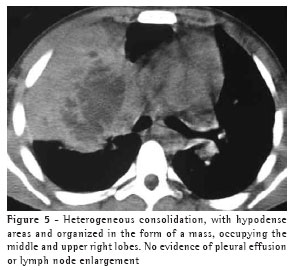

The most frequent finding in the imaging, present in the seven patients, was ill-defined consolidation (Figures 1, 2, 3 and 4). Five of patients presented air bronchogram, principally at the periphery of the lesion. In three cases, the consolidation was organized in the form of a mass. In six of the seven patients, irregular areas of cavitation were observed within the consolidations. Multiple cavitations were seen in five patients, and a singular cavitation was observed in one patient. In the patient presenting no cavitation, there were hypodense areas suggestive of necrosis (Figure 5). Only one of the patients presented air-fluid levels within the cavities.

Small centrilobular nodular opacities presenting a 'tree-in-bud' pattern, predominantly encircling the area of consolidation, were observed in three patients. In one of those patients, the lesions were also found in the hanging portions of the lower lobes. Peribronchial nodules, tending toward confluence and located in the periphery of the pulmonary consolidations, were observed in four cases.